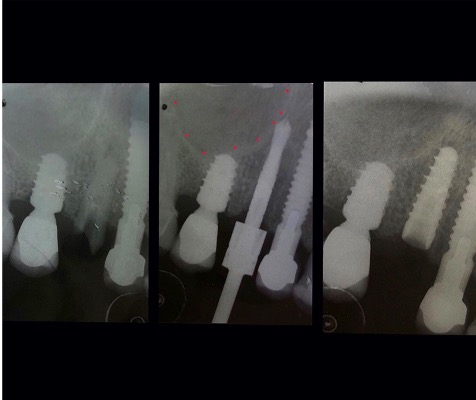

Un impianto dentale o fixture è un corpo in titanio, totalmente biocompatibile, che viene posizionato nella mascella o mandibola con lo scopo di sostituire la radice di un dente naturale perso. Su di esso viene successivamente o immediatamente quando possibile (carico immediato) fissata la protesi ovvero la corona del dente restituendo funzione ed estetica.

Gli impianti non hanno scadenza quindi non sono un rimedio temporaneo ma una soluzione definitiva per tornare ad avere denti come quelli originali. L’osteointegrazione è così forte e perfetta che se volessimo rimuovere l’impianto in un secondo momento dovremmo togliere anche l’osso che lo circonda.

Il carico immediato è possibile quando l’osso ha una qualità tale da dare una stabilità meccanica immediatamente adeguata all’impianto.